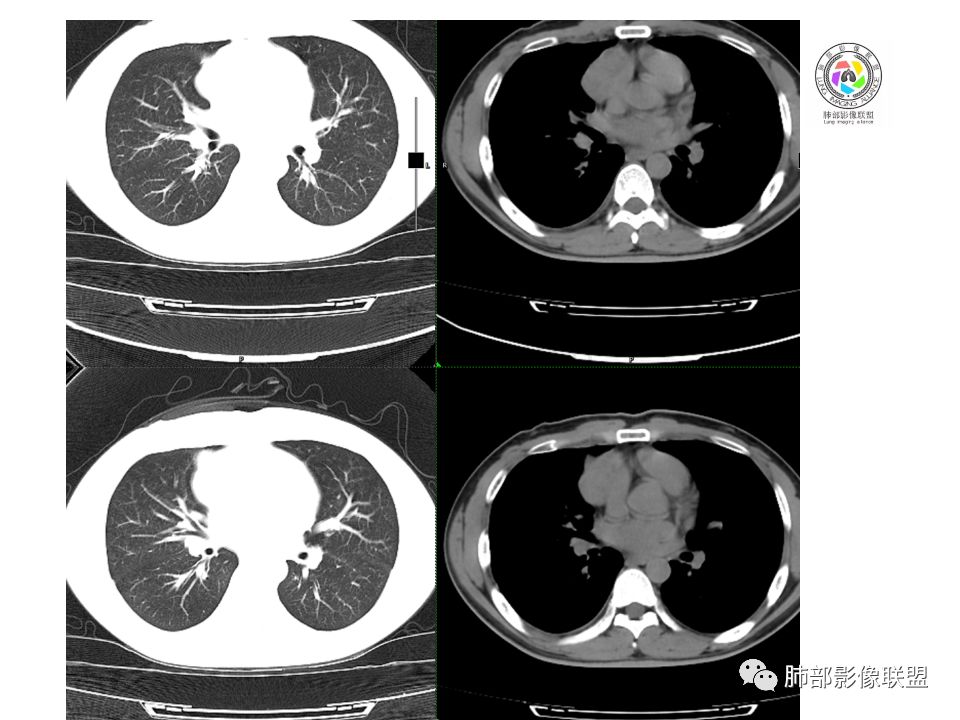

晨读:前纵隔占位,密度不均,沿着右侧纵膈延伸到肺门水平,周围支气管推移,大血管向内推移。临床有重症肌无力,考虑胸腺瘤可能,鉴别淋巴瘤。

患者青年人,前纵隔占位,无增强,猜一个淋巴瘤,不知道右下肺膨胀不全原因是什么

右前纵膈肿块,偏一侧生长,形态欠规则,密度不均匀,其内可见小点状钙化,双肺多发小叶中心结节及钙化灶,右侧胸膜增厚(有陈旧性结核可能),青年男性(27岁),没有增强,考虑,1,前纵隔生殖细胞瘤2,精源细胞瘤

右前上纵隔占位,瘤肺交界面清楚,提示纵隔来源,其内有点状钙化,右侧胸腔积液,有临床症状,年龄轻,考虑生殖来源可能,胸腺瘤待排,请结合临床相关检查或CT增强进一步检查。

前纵隔占位,伴点状钙化;上腔静脉后移位。伴右胸膜局限性增厚,临床有重症肌无力,病人年轻,考虑胸腺瘤可能,鉴别生殖源性肿瘤。

临床症状眼睑下垂,右纵膈占位,偏向一侧,有分叶,跟上腔静脉边界不清,淋巴结肿大,考虑胸腺瘤或胸腺癌

右前纵隔占位,有分隔`低密度、点状钙化,边缘光滑,侵袭心包不明确,伴右胸少量积水,考虑恶性,生殖源性可能大,有视物不清,是否脑转移待查。建议HCG丶AFP检查。鉴别1:胸腺瘤、癌,30一40岁以下,少见,但有眼脸下垂,肌无力,待排除。2:淋巴瘤:侵袭性不强,有点状钙化,不支持。3:畸胎瘤:有低密度丶钙化,建议增强进一步明确。4:神经源性:一般后纵隔常见,不支持。5:LCD:症状少见,可以有树枝状钙化,浆细胞型可以有低密度,增强进一步明确

前纵隔偏侧肿块,病灶内见点状钙化,症状肌无力,考虑恶性,胸腺瘤或神经内分泌癌

没有增强,好像两个病灶,上方三角形的像是胸腺增生。下方肿块,没有增强显得更难了,微钙化,轻度分叶,像有坏死低密度影,右侧少量胸水,胸膜受侵.,有视物模糊眼睑下垂。考虑胸腺瘤B1型及以上、B2型可能或生殖细胞瘤

患者年轻,有肌无力症状,除肿块外,前纵隔密度增高,与心包界限不清,考虑恶性。

前纵隔右区占位性病变,上区与胸腺延续,下区呈分叶状,尽管年龄<30还是首先考虑胸腺瘤,侵袭性可能性大(眼睑下垂不知是否有关)。鉴别主要是生殖细胞类肿瘤,主要是精原细胞瘤。另左肺上叶结核球,右侧胸腔积液,需除外结核性胸膜炎和转移

前纵隔占位性病变,偏向一侧生长,密度不均,可见点状钙化,考虑胸腺瘤,鉴别精原细胞瘤

右前纵隔肿块,边界清楚,密度欠均匀,内似有分隔和低密度区,似有多结节融合,几乎从上到下,年龄较轻,不是胸腺瘤好发年龄,但却有视物模糊,眼睑下垂症状,考虑淋巴瘤?鉴别胸腺瘤?结核?

右前上纵膈肿块,内有点状钙化和少许小片状坏死,局部边界似欠清,右侧胸膜腔少量积液,年轻男性,小于30岁,有重症肌无力,虽然年龄偏轻,仍先考虑胸腺瘤,代排生殖源性肿瘤

晨读前纵隔肿块,偏右侧,密度不均,见点状钙化灶及分隔状低密度影。胸腺瘤>生殖细胞瘤>淋巴瘤

前纵膈占位,上腔静脉受推移,有分叶密度较均匀,结合临床考虑胸腺瘤,待排生殖细泡瘤.淋巴瘤

前中纵隔(胸腺癌区)不规则肿块,密度不均,有坏死区、点状钙化,边缘不会整肿块偏向右侧,向心包流注感,右胸腔少量积水。患者27岁,重症肌无力表现。